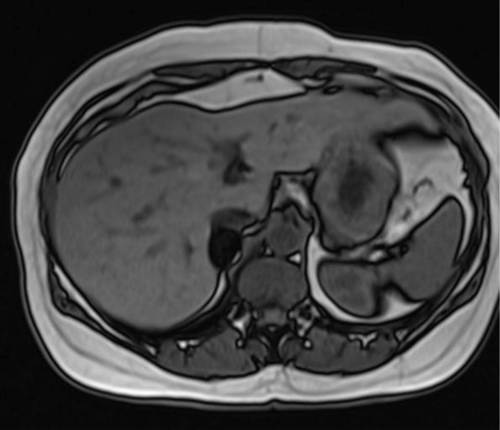

A 45-year-old male is found to have an incidental right adrenal lesion on CT. An MRI was arranged for further evaluation.

1. What sequences are shown?

2. Describe the findings.

3. What is the likely diagnosis?

- T1 weighted axial MRI in-phase and out-of-phase. Fluid is dark on T1 images, and the cerebrospinal fluid (CSF) in the spinal canal is seen to be dark. When assessing for the type of sequence, looking at vessels can be misleading as they are usually dark due to flow void.

- There is a well-defined nodule seen in the right adrenal gland. It appears solid on the in-phase image and demonstrates complete loss of signal on out-of-phase image.

- The diagnosis is an adrenal adenoma. Loss of signal on out-of-phase imaging is due to chemical shift artefact, caused by the composition of the lesion. An adenoma contains intracellular fat, which causes the loss of signal. It is not composed of macroscopic fat, otherwise it would be bright on both T1 and T2 MRI.